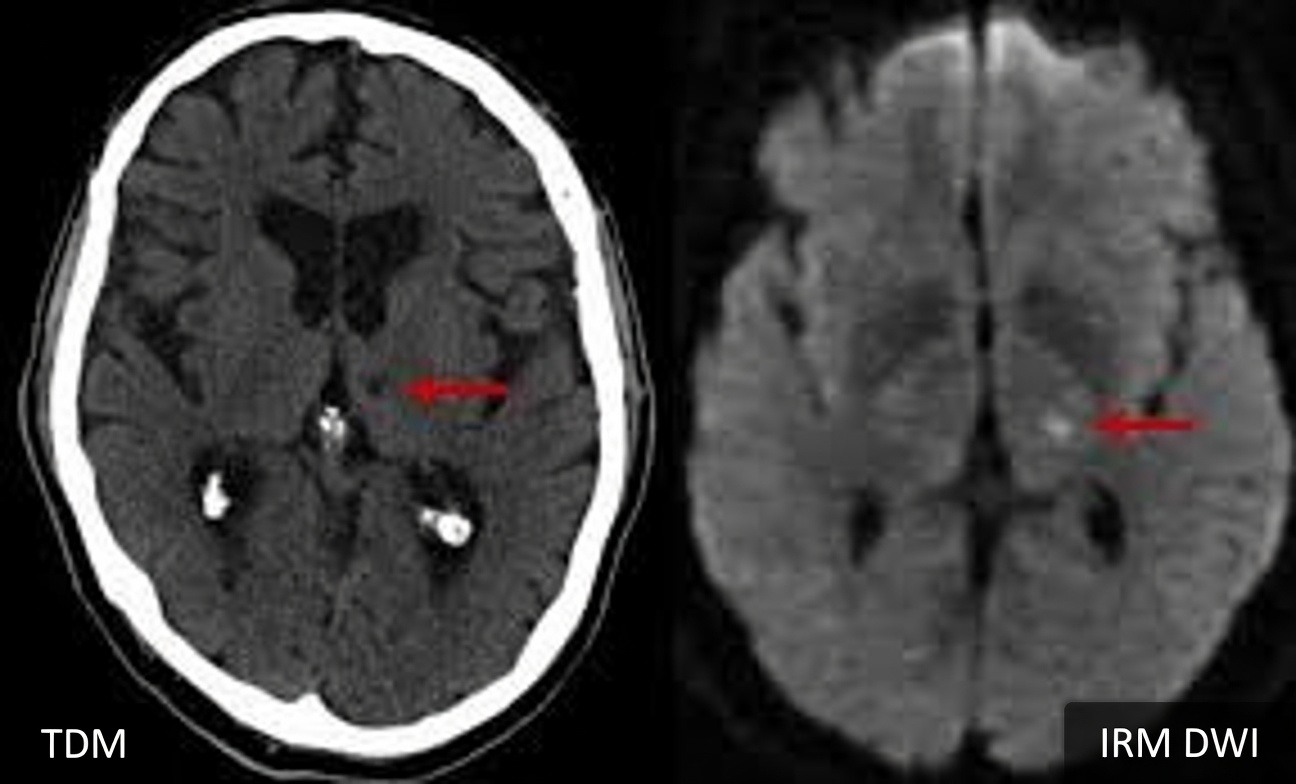

Les signes avant-coureurs de l’AVC lacunaire apparaissent lorsque de minuscules artères situées en profondeur dans le cerveau se bouchent. Cela crée de petites cavités (lacunes) qui endommagent des zones cruciales comme les ganglions de la base et le thalamus.